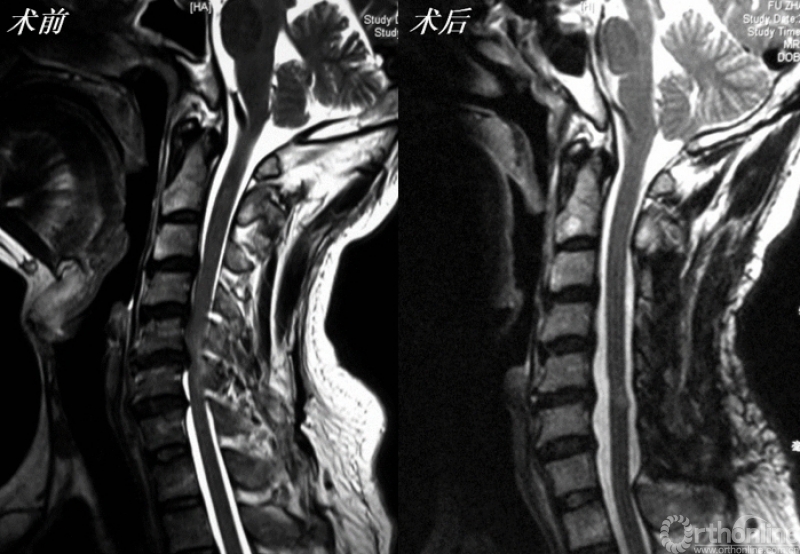

针对“门轴”的固定方式以及后方软组织结构破坏等问题衍生了多种改良术式,但这些术式的减压原理相同:(1)直接减压效应:直接去除来自脊髓后方的压迫(如黄韧带肥厚、骨化、钙化)或纠正发育性颈椎管狭窄;(2)间接减压效应:在临床实践中,人们发现椎管扩大之后,脊髓会发生后移,从而消除或减弱了来自前方的压迫(如椎间盘突出、后纵韧带骨化、椎体后缘骨赘等)对脊髓的影响(图1)。

图1